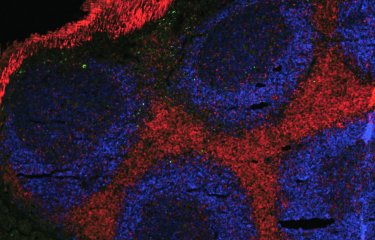

What is the current state of research into female cancers? That's the question we were asked on the street.

Aurélie Chiche, a researcher at the Institut...